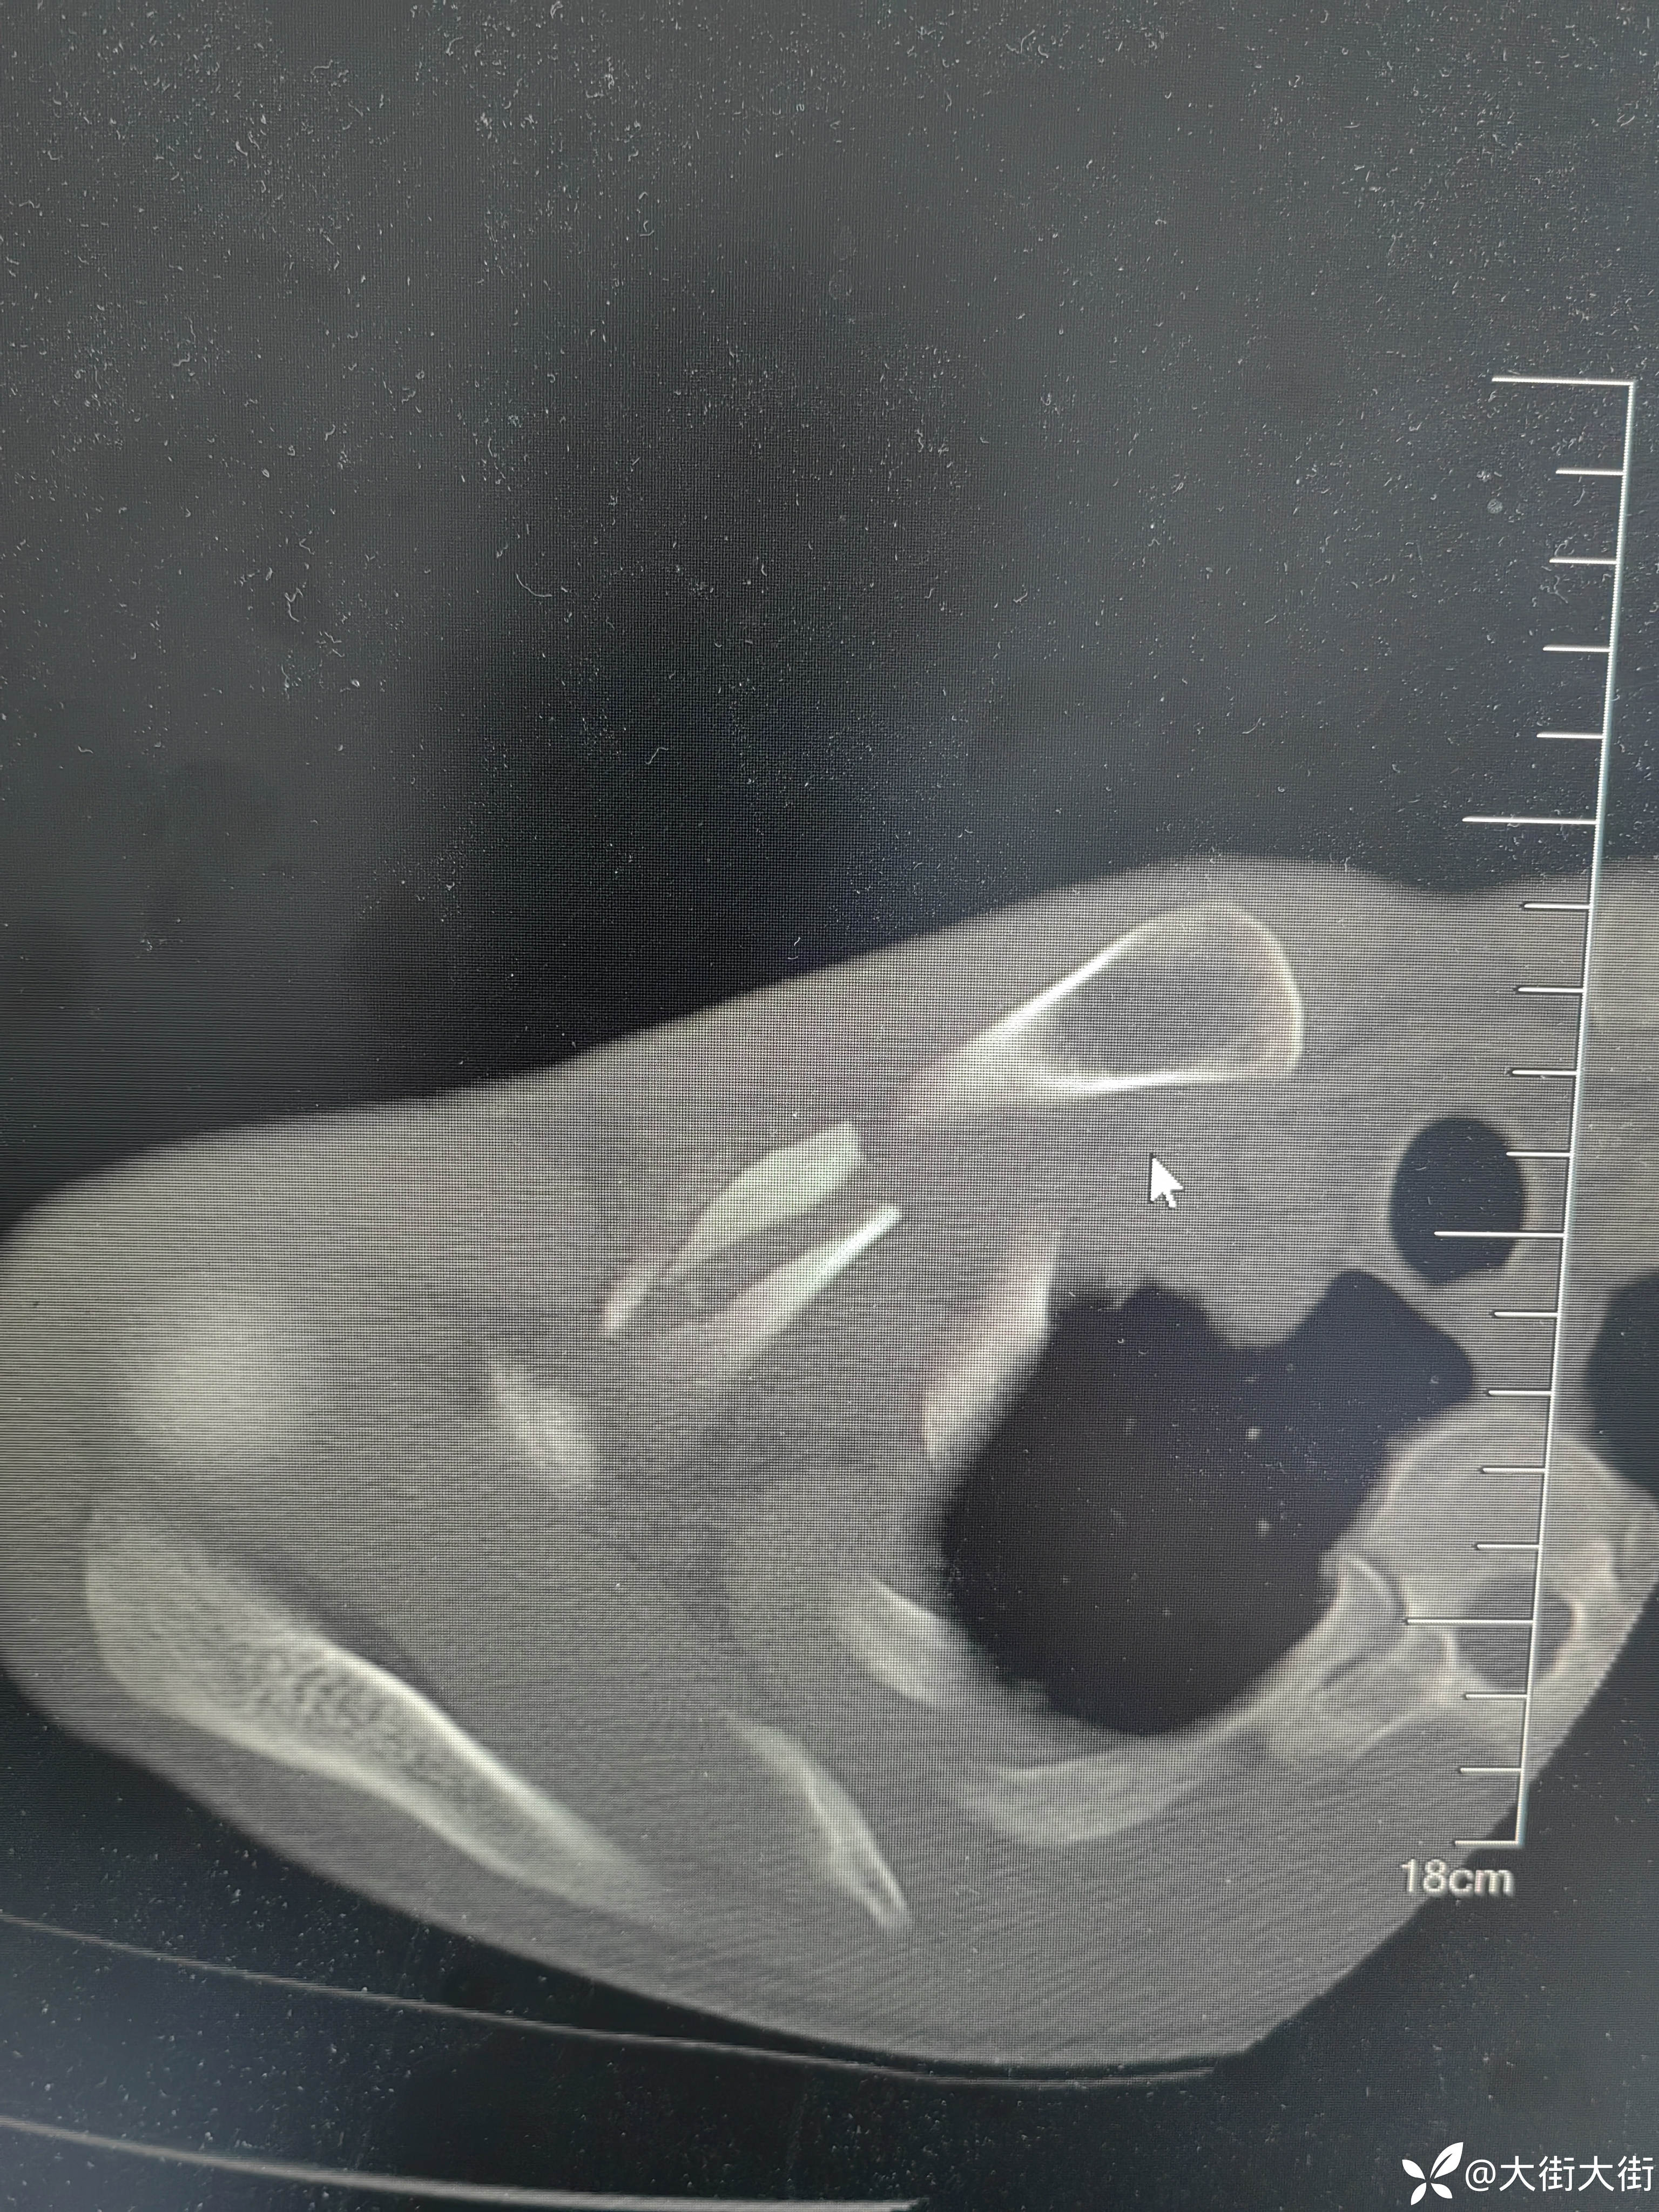

【患者信息】:男,61岁

【主诉】:外伤致右肩部疼痛,活动受限3天。

【临床诊断】: